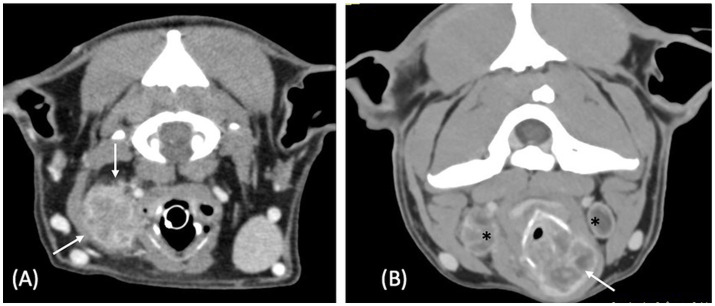

Results: Four dogs had laboratory reports compatible with a malignant neoplasia and three with an inflammatory process. The shape of the mass was defined as "ovoid" in all neoplastic masses and as "thickening" in cases of inflammatory processes. Masses were of various sizes (median length: 42 mm, range: 26-82 mm) and either unilateral (1/4 and 2/3 of neoplastic and inflammatory masses respectively) or bilateral. They were described as mineralized (1/4 and 1/3) and as having either an internal (1/4), external (2/4) growth pattern or both (1/4, 3/3). All masses had ill-defined margins and showed heterogeneous contrast enhancement. Two neoplastic and two inflammatory masses had a cavitary aspect. All but one case were associated with regional lymphadenopathy. Thyroid cartilage destruction was observed with two neoplastic and two inflammatory masses.

Clinical relevance: This case series describes CT features of laryngeal masses. The shape of the laryngeal mass may assist in determining its nature, inflammatory process was defined as "thickening" of the larynx and neoplasia as "ovoid"-shaped, whereas other studied features were inconsistently observed in both neoplastic and inflammatory conditions.